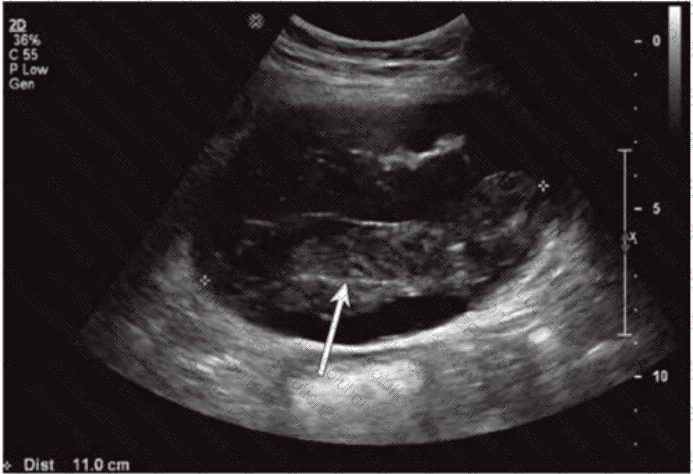

Which condition of the transplant kidney is indicated by the arrows on these images?